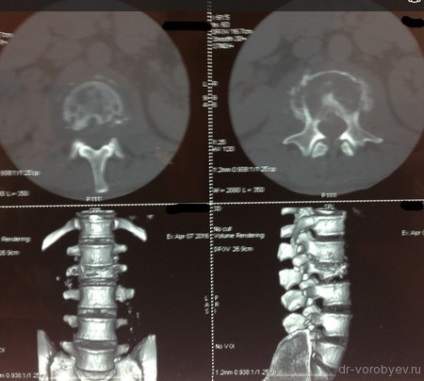

La filmele de control după implanturi chirurgie bună stare, decompresie este realizată în mod adecvat.

Doar după terapia cu antibiotice masive, pacientul a suferit o intervenție chirurgicală: corporectomy C6, C7. Cage Corporodesis alunecare (corp vertebral protetice) ADD + Ulrich, Germania și înlocuitor de os de corali. Pe CT de control în picioare implanturi decompresie corectă, adecvată.